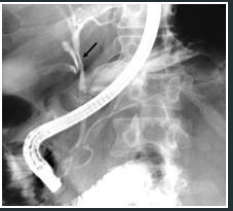

O EXAME DEMONSTRADO É :

1.URETROCISTOGRAFIA RETRÓGRADA ( CONSIDERAR CONTEXTO DO TRAUMA )

2.DEMONSTRA LESÃO DE URETRA .

LEMBRANDO QUE NESSE CASO , NÃO PODEMOS FAZER CATETERIZAÇÃO VESICAL .

* SE A URETROCISTOGRAFIA ESTIVESSE NORMAL DEVERÍAMOS REALIZAR CISTOGRAFIA.